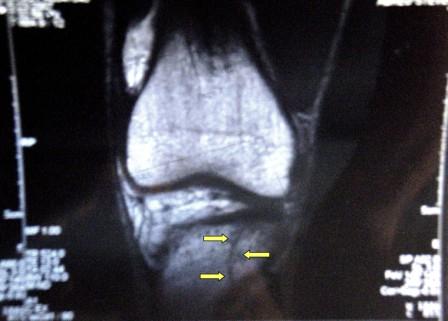

Comments: My wave was the VERY last one after 2000+ people went off, but I didn’t really care. I was ready and looking forward to race. Went the gun went off I start running into the water at the front of the pack because it was a beach start. While running my left leg landed on a hole in the sand and my knee hyper extended backwards and I felt a pop right away, but I didn’t stop (I ended up getting a fracture on my femur but didn't know of course). I began swimming and got into a rhythm really fast. I stayed next to the buoys all the time and swim comfortable passing LOTS of people. That slowed me down a bit as I had swim around many athletes but all in all I was moving. I hit the 1st turn around at 11:30 min. Then the right knee start hurting but the pain was manageable. I kept on swimming and hit the 2nd turn around back to the beach. I swam steady but as I got closer I look at my watch and I was over my goal WTF? I got disappointed but kept on swimming. I clocked 31+ min but after chatting with some pros the general consensus was that the swim was long at least a couple of 100s. What would you do differently?: nothing conisdering the pain in my knee.  Transition 1

Comments: This was the toughest part of the race, not because I ran out of gas but because of the busted knee. As soon I started running it was obvious the pain was not going away but the opposite, it was getting worst. I tried to focus on my form and clocked a 6min mile for the 1st mile (right on target) then I got into the trail run section and my knee pain become very bad. When I got to mile 2 my pace felt to 6:20s and at that point I wasn’t even thinking about my pace but questioning whether I should continue or not. I kept running and I decided to DNF as soon as I would complete the 1st loop and get to see Jess and the rest. I even began thinking of ways to explaining them that I busted my knee and that I wasn't quitting because I was just giving up on the fight. I got to mile 3 and drank coke, water, G-ade and took 4 salt pills and kept moving and then it hit me; I was still passing people even though I was now running like 6:30s per mile. Fitness wise I was feeling awesome, sort of like I was jogging along on a training run, but I couldn’t speed up cuz of my knee. I got to the turn around and the BTers were cheering loud! It was very motivating and right there I decided to attempt another loop. At that point my friend Phil was getting into his 1st loop of the run and I told him my knee was busted and maybe I should quit. He told me, he had some Advil and I just nodded in acceptance and got like 3 or 4 pills which I just drank in the next water station along with 4 more salt tablets, coke and a gel. I kept on moving and the 2nd loop was a struggle cuz again I was feeling awesome but I couldn’t ruin fast cuz the knee was hurting badly. I think I passed Dan at some point in that loop cuz someone mentioned my name and encourage me but I was so out of it that I am not sure who was it. My pace by then felt to 6:50s on the 2nd loop. I reached the turned around for the 3rd loop and when I saw the BTers again I couldn’t control it and start crying because of the the pain and the cool feeling I got from their cheers. That propelled me into the 3rd and final loop. I saw my friend Phil once again and he just said: you can outrun many of these guys even with a busted knee so chop chop mother F-cker. That made mi laugh + the fact that the Advil might have kicked in by then I began running more comfortable. The next mile my pace improved to 6:15s, then the next to 6:05s and the next one was 5:55s when I reached the last water station. I just grinded my teeth and kept on moving and clocked a 5:40s for the last 1.2 mile! What would you do differently?: Not cry in front of the BTers :)  Post race Warm down: my warm down consited in a pic with trixie and shannon which in reality it just warmed me up again! ;) What limited your ability to perform faster: uuuummmmm just a sprained knee but that's it ;) Event comments: I am VERY happy with the race. 5 months ago I was uncertain about been able to train and 3 months ago I was uncertain about when I was going to be able to get back in good racing shape. Considering all that plus the fracture on my femur, I couldn’t be more pleased with my race execution and result. Still I have mixed feelings cuz after learning that I have a fracture on my femur it makes me questioned my desicion of finishing. Now I'll be out of actino for 4-8 weeks but i hope at least I can do some swimming to avoid loosing all my fitness THANK YOU VERY MUCH to Jess, Jeff, Trixie and Shannon for the awesome cheering and support. Thanks to Philip for been my race drug dealer (and congrats on the killer PR) Mac, Dan and Mimi it was very fun meeting you (and Dan, you definitely have issues!) Last updated: 2007-04-05  12:00 AM |